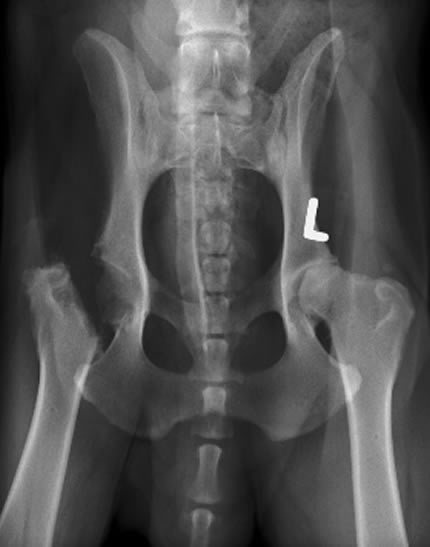

Femoral head osteotomy (FHO) is the surgical removal of the ball and neck of the femur, in the hip joint.

It is used in cases of

- advanced hip dysplasia where the hip joint has also become arthritic

- in complex fractures

- cases of avascular necrosis (lack of blood supply to the bone–a genetic condition called Legg Calve-Perthes, seen mostly in toy breeds is an example of avascular necrosis)

Triple pelvic osteotomy (TPO)

TPO is available for young dogs up to 1 year of age. It nvolves cutting and re-positioning the bone and re- angulation of the joint

Total hip replacement (THR)

Total hip replacement (THR) inserts an artificial hip (endoprosthesis), and is used in dogs over 1 year of age.

Indications for FHO

The FHO becomes, if not the optimal treatment of choice, an economical solution with a shorter recovery period.

It is performed more on smaller dogs, less than 40 pounds. It is not highly recommended for large dogs.

When the FHO is performed, it allows a false joint to form in place of the normal ball and socket.

From that point on the “hip” is biomechanically altered and the leg becomes shortened. Even with physical therapy and rehab, there can be some recurring deviations and lameness in gait with less weight borne on the leg than before the surgery.